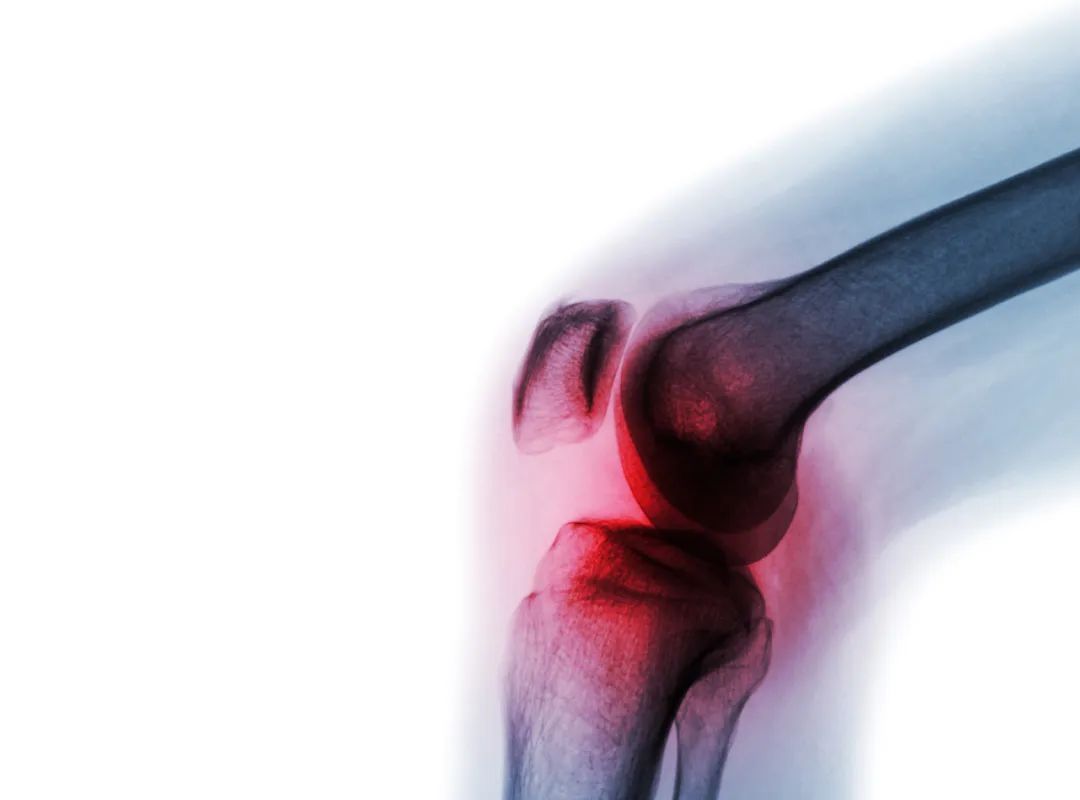

骨關節炎就是一種由于年齡增大、關節勞損、創傷等諸多因素引起的關節軟骨退化、關節骨質增生為特征的退行性病變。

隨著年齡的增長,越來越多的人出現腰背痛、膝蓋痛,尤其是上下樓時,膝蓋疼痛明顯,在休息后減輕,大多數老年人把這種狀態叫做“風濕”,但是其實準確來講,很大可能這種情況是患上了“骨關節炎(OA)”。